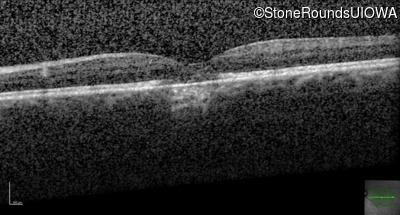

Optical Coherence Tomography - Right - 20/20 +2

Exemplar / OCT Stack

Optical Coherence Tomography - Left - 20/40 -2